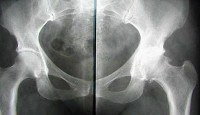

Для коксартроза 1 степени характерны периодические боли, возникающие после физических нагрузок (продолжительная ходьба или бег). В основном боль концентрируется в области тазобедренного сустава, реже возникает в области бедра и коленного сустава. Обычно после отдыха боль проходит. Амплитуда движений при этом не ограничена, походка не нарушена, мышечная сила не изменена. Если сделать на этой стадии пациенту рентген, то видны незначительные костные разрастания, но при этом не выходящие за пределы суставной губы. Костные разрастания располагаются вокруг внутреннего или наружного края суставной поверхности вертлюжной впадины. Шейка и головка бедренной кости практически не изменены. Суставная щель неравномерно сужена.

При коксартрозе 2 степени боли усиливаются и носят более интенсивный характер. Помимо болей в самом суставе, они отдаются в паховую область, бедро и возникают даже в состоянии покоя. Длительная ходьба вызывает хромоту. Нормально функционировать сустав уже не может. Значительно ограничивается внутренняя ротация и отведение бедра. Отводящие и разгибающие бедро мышцы теряют свою былую силу. На рентгенограмме пациента видны уже значительные костные разрастания как по внутреннему, так и по внешнему краю вертлюжной впадины, выходящие за границы хрящевой губы. Головка бедренной кости деформируется, увеличивается в объеме и имеет неровный контур. В самых нагружаемых частях головки и вертлюжной впадины возможны образования кисты. Шейка бедренной кости расширяется и утолщается. Щель тазобедренного сустава неравномерно сужается (до 1/3 - 1/4 начальной высоты). У пациента наблюдается тенденция к смещению головки тазобедренной кости к верху.

Боли при коксартрозе 3 степени носят уже постоянный характер, возникающий даже ночью. При ходьбе больному необходимо использовать трость. Движения в суставе резко ограничены, мышцы бедра, голени и ягодицы - атрофируются. Из-за слабости отводящих мышц бедра, происходит наклон таза во фронтальной плоскости, что приводит к укорочению конечности на больной стороне. Чтобы при ходьбе достать до пола, больному приходиться наступать на пальцы стопы и наклонять свое туловище на больную сторону. Именно таким образом приходиться компенсировать укорочение конечности и наклон таза. Но способ компенсации ведет к перемещению центра тяжести и к сверхнагрузкам на сустав. На рентгенограммах видны обширные костные разрастания со стороны головки бедренной кости и крыши вертлюжной впадины. Суставная щель резко сужается. Шейка бедренной кости значительно расширена.